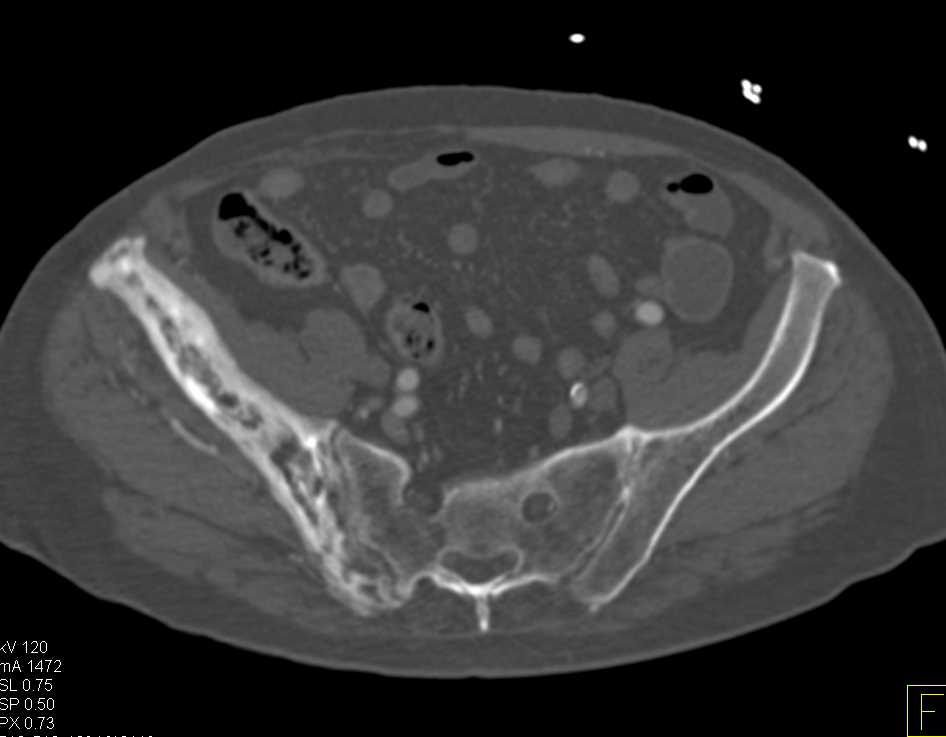

Diagnosis

Normal Temporomandibular Joints (TMJ)